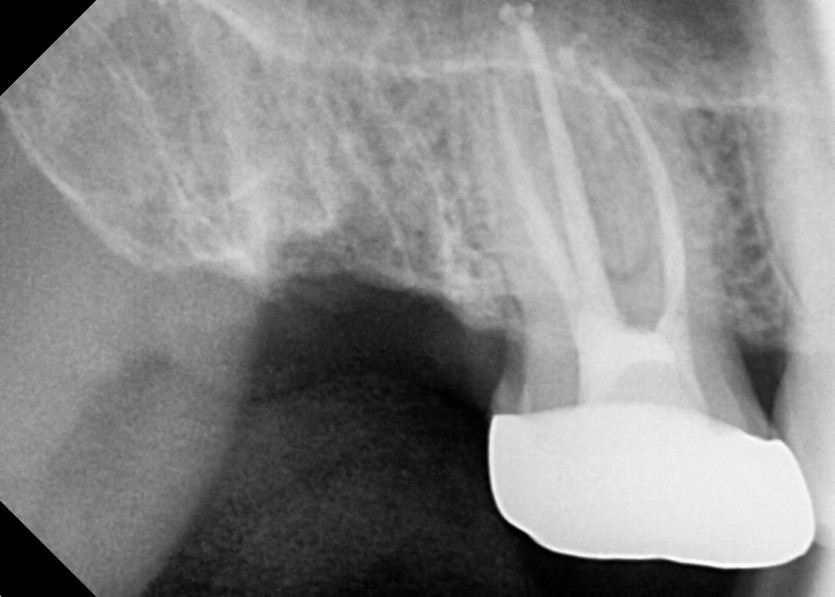

#18,48 사랑니 발치

구강 외과 전문의가 당일 발치했습니다.